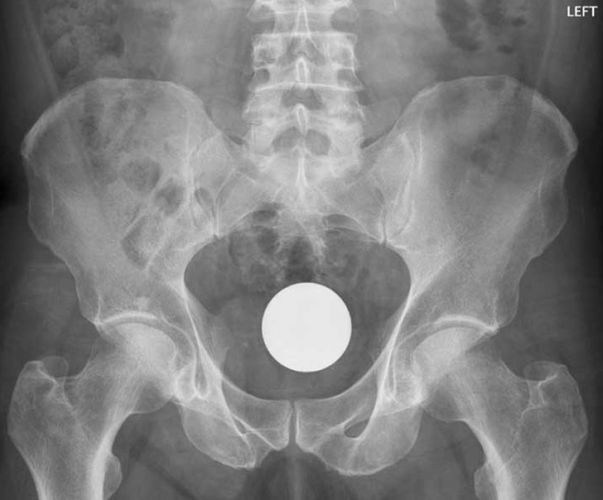

Bola de Bilhar